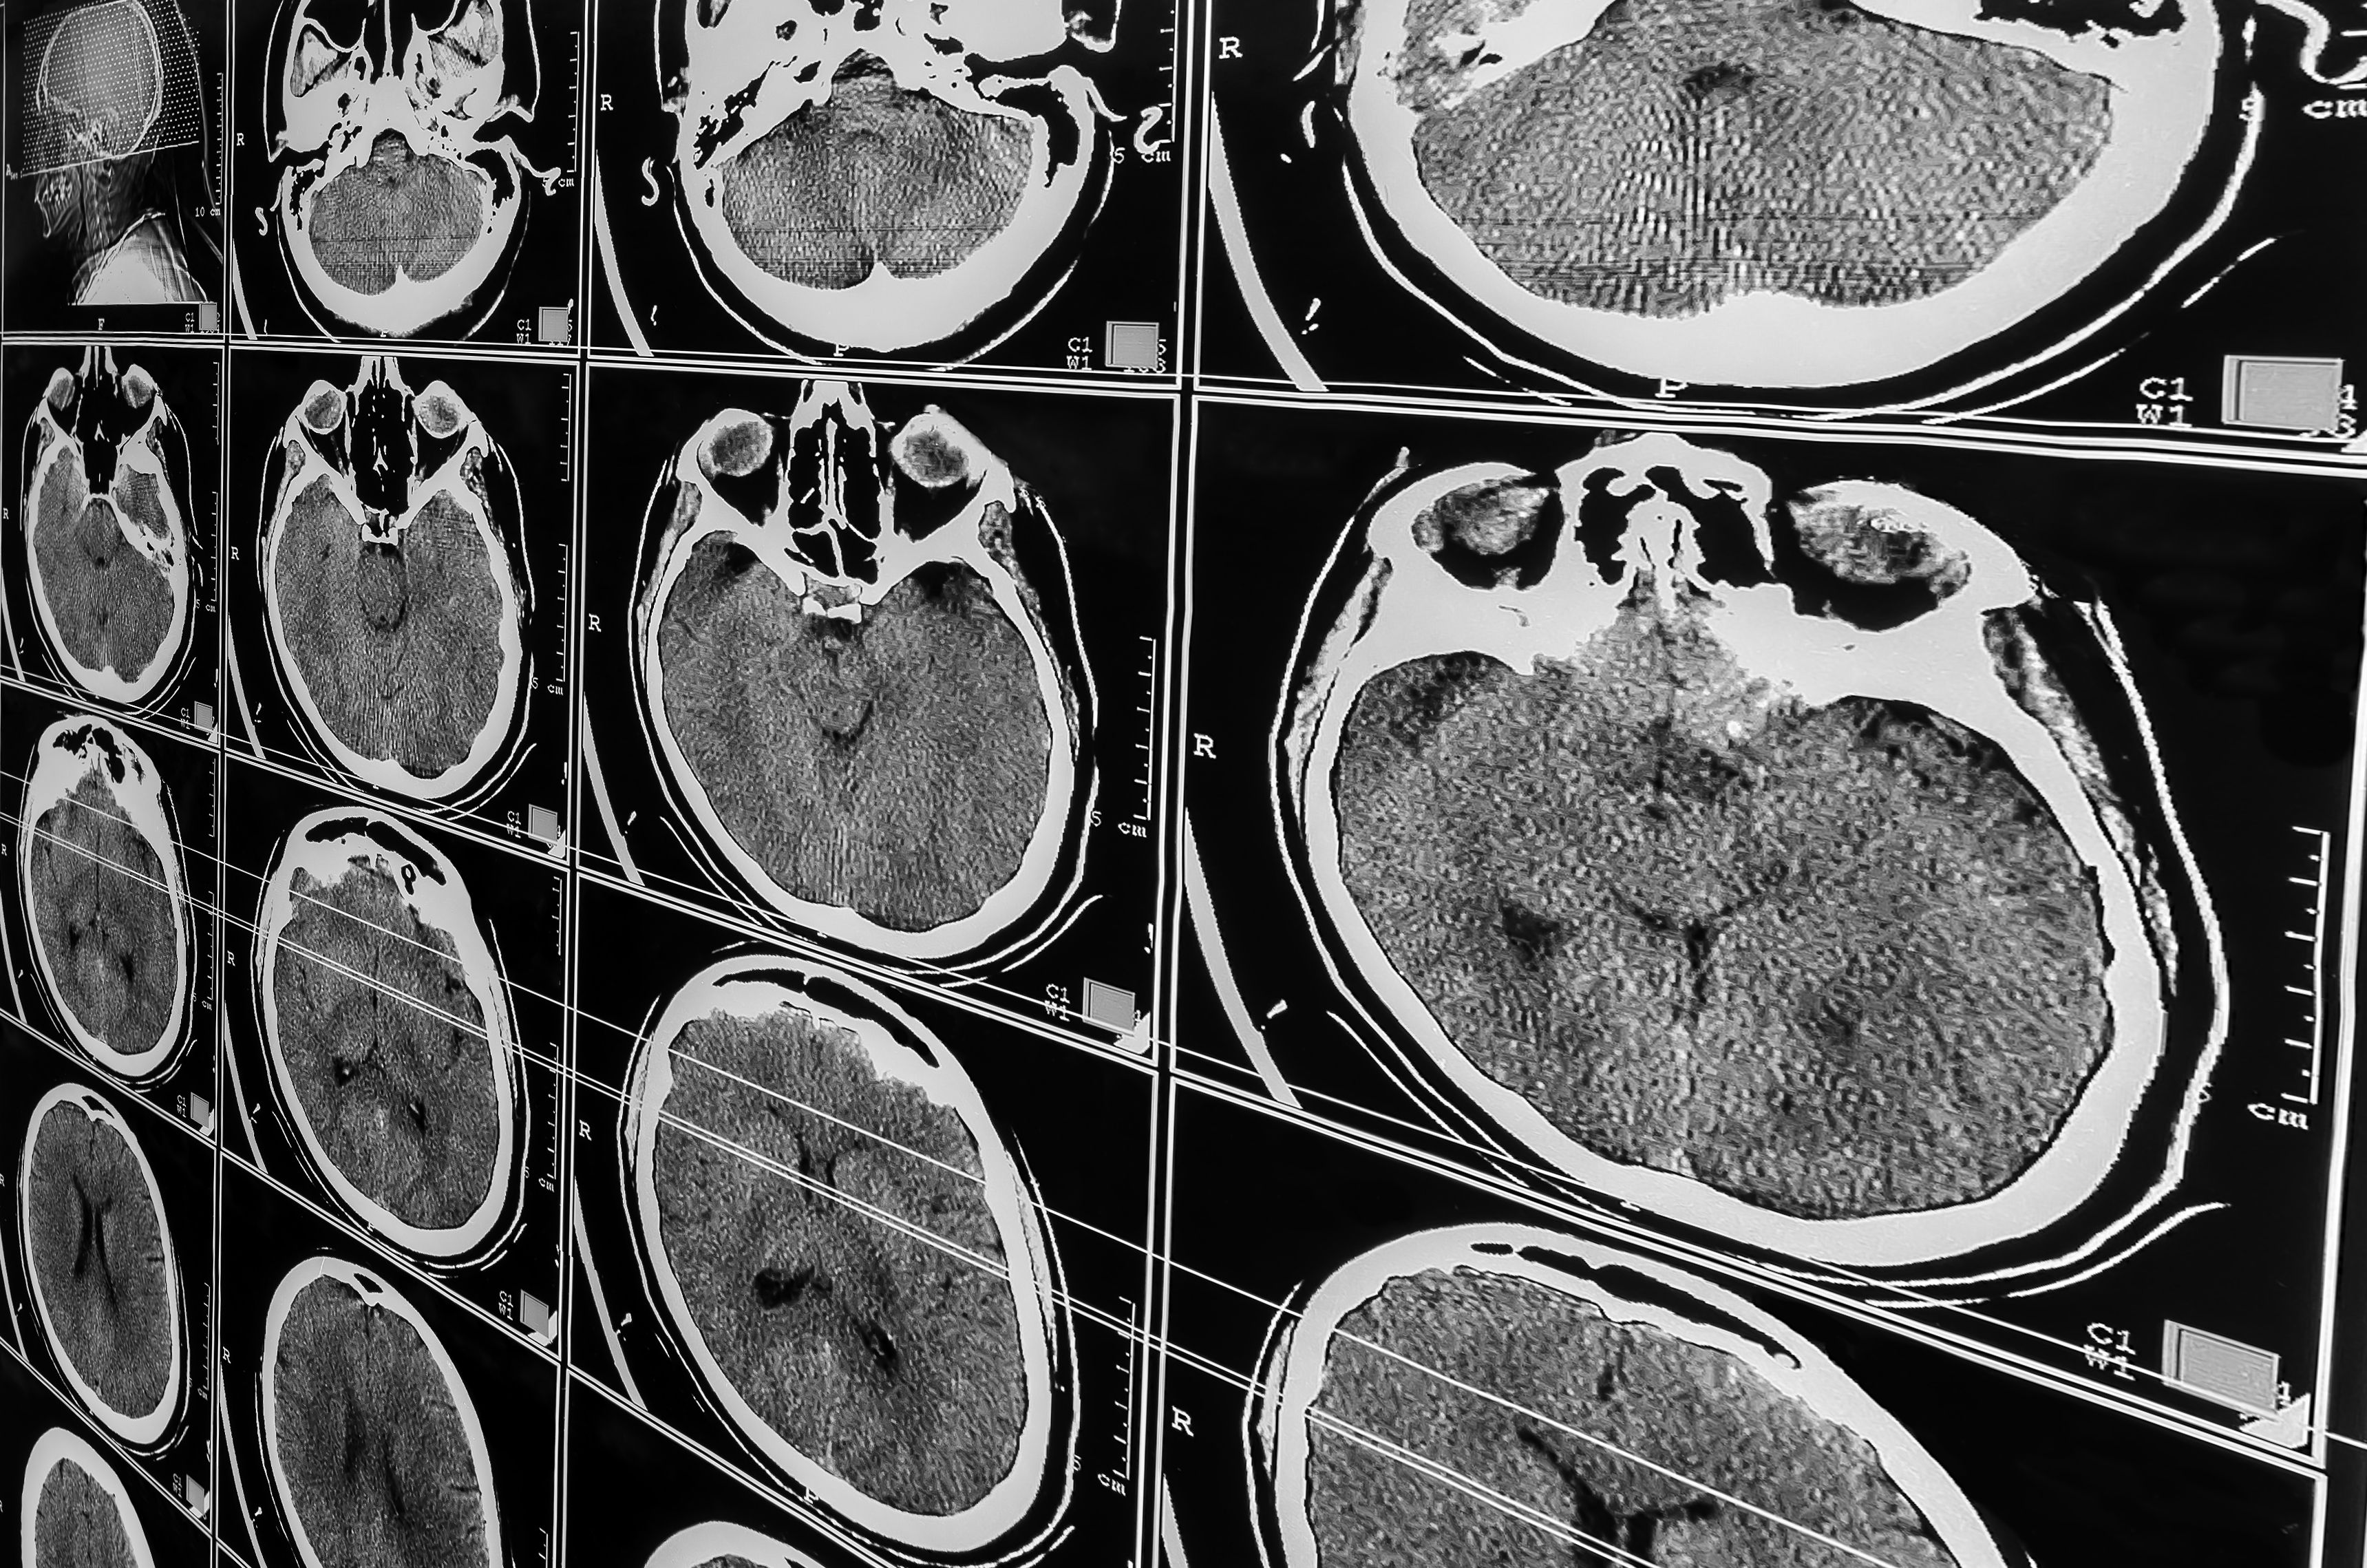

Investigadores españoles descubren una nueva alteración en el cerebro de las personas con Alzheimer

Investigadores del Instituto de Neurociencias UMH-CSIC, en Alicante, han descubierto una nueva alteración en el cerebro de las personas con Alzheimer. El hallazgo abre la posibilidad de encontrar a corto plazo un buen biomarcador diagnóstico y a largo plazo de intervención terapéutica.